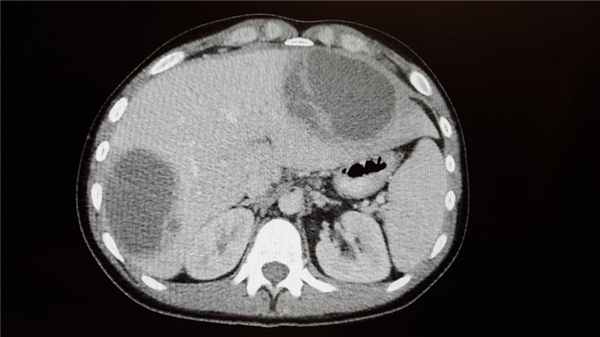

КТ органов брюшной полости

При подозрении на абсцесс методом выбора является КТ брюшной полости и таза с пероральным контрастированием. Другие способы визуализации также могут выявить некоторые изменения; при обзорной рентгенографии брюшной полости может определяться газ в полости абсцесса, смещение соседних органов, мягкотканное образование, соответствующее абсцессу, либо исчезновение тени подвздошно-поясничной мышцы. При расположении абсцессов вблизи диафрагмы могут наблюдаться изменения со стороны грудной клетки, такие как плевральный выпот, высокое стояние и снижение подвижности купола диафрагмы, инфильтрация в нижней доле, ателектаз на стороне поражения.

Абсцессы могут располагаться в любой части брюшной полости и забрюшинного пространства. Чаще они развиваются после хирургических вмешательств, травм, инфекционно-воспалительных заболеваний органов брюшной полости, особенно сопровождающихся развитием перитонита и перфорации. Проявления включают общую слабость, лихорадку, боль в животе. Диагноз ставится на основе КТ. Лечение подразумевает хирургическое или чрескожное дренирование. Дополнительно назначают антибиотики.